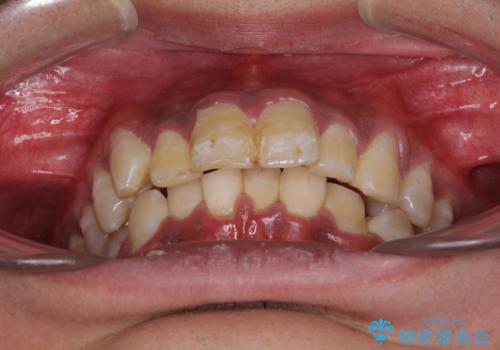

深い咬み合わせと前歯のデコボコ ワイヤー装置での抜歯矯正

- 深い咬み合わせと前歯のデコボコを改善したいとのことで来院された患者様です。

口元の突出感はないものの、上顎前歯のデコボコが著しく、右側の咬み合わせがずれていたため、上顎右側第一小臼歯1本を抜歯することとしました。

咬合力が非常に強く、抜歯したスペースがなかなか閉じないであろうことは予想できましたが、思っていた以上に期間がかかりました。

前歯のすり減りも著しかったため、仕上げの位置の調整にも期間を要しました。